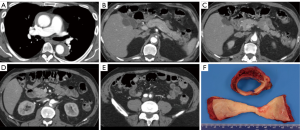

From April 1998 to April 2018, 644 patients underwent upfront endovascular fenestration/stenting for MPS or emergent aortic repair of an ATAAD or IMH (ATAAD/IMH defined as onset within 14 days of admission); 82 (13%) with a type A IMH (defined as IMH without a double lumen in the ascending aorta) (Figure 1), comprised the focus of this study. Among those with ATAAIMH, 12 presented with MPS and 70 presented without MPS. This cohort includes patients with small and sometimes subtle intimal tears with no or minimal sub-intimal contrast spillage and with or without segments of descending thoracic or abdominal aorta with patent false lumens.

MPS is different from malperfusion. A diagnosis of MPS entails end-organ dysfunction and requires both clinical and laboratory features (neurologic deficit, abdominal pain, bloody diarrhea, tenderness to palpation, elevated lactate, troponins, liver enzymes, metabolic acidosis, etc.) in addition to radiographic demonstration of decreased or absent blood flow to a vascular territory (brain, coronary, liver, bowel, kidneys, extremities, etc.) (Figure 1). Patients with endovascular-amenable MPS (visceral and extremities, n=10) and without evidence of aortic rupture or cardiac tamponade (indications for immediate aortic repair) were treated with upfront endovascular fenestration/stenting prior to aortic repair. Patients with cerebral (n=1) and coronary (n=1) MPS were managed with emergent open repair as previously described (14,15).

The development of malperfusion and MPS in ATAAIMH remains an incompletely answered question. Additionally, the mechanism of ATAAIMH is unknown: it has been suggested that it could originate from rupture of the vasa vasorum (24,25) or thrombosed false lumen of aortic dissection. More and more evidence point toward the latter with an intimal tear identified in IMH cases (3,26,27). When we operate on ATAAIMH, the thrombosed false lumen of the ascending aorta is identified in all cases. Whether the ATAAIMH developed from ruptured vasa vasorum or intimal tear, when patients develop full-blown ATAAIMH, the thrombosed false lumen can extend into any branch of the aorta, causing malperfusion and subsequent MPS. However, the incidence of MPS in ATAAIMH (15%) is lower than that in ATAAD patients (30%) (14). In ATAAIMH patients, when the false lumen is completely thrombosed throughout the aorta, there can be no dynamic obstruction of the aortic branches or dynamic malperfusion of end-organs. Most of the malperfusion in ATAAIMH is static and occurs when the aortic branches are involved with IMH (Figure 1), and cannot reliably be resolved by open aortic repair. This is different from malperfusion in ATAAD, which can be dynamic or static. Therefore, malperfusion with MPS (tissue/organ necrosis and end-organ dysfunction) in ATAAIMH may require revascularization to resolve malperfusion before aortic repair, since proximal aortic repair does not significantly alter flow or increase perfusion pressure in the descending aorta and therefore, cannot predictably resolve static malperfusion. As noted above, type A IMH as well as classic type A dissection can be accompanied by segmental false lumen thrombosis distally, such as at the aortic bifurcation, and in these cases, fenestration is used to arrest retrograde false lumen thrombosis, with stenting necessary to resolve any persisting static obstruction. In summary, endovascular fenestration/stenting can treat the anatomical spectrum of MPS accompanying IMH, and is the treatment of choice except when there is significant coronary or neurovascular compromise.